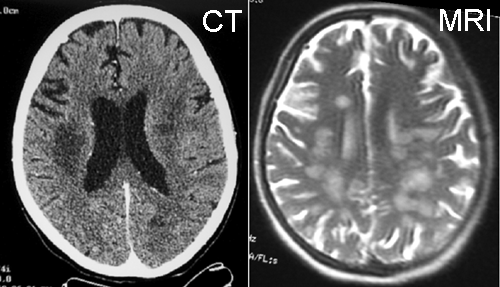

The impression at admission was possible left MCA stroke.  A panel of studies were performed which included head imaging.  The initial CT was said to be normal.  MRI scan revealed multiple hyperintense lesions on T2-weighted images and diffusion images which suggested leukoencephopathic changes. Similar changes were present in the CT that was obtained in the later course of the disease. MR-angiogram (MRA) showed abnormal vasculature.

On CT scan, there is multiple hypodense white matter lesions that appear to spare a thin layer of subventricular white matter (Panel A). The T2-weighted images on MRI provides a more accurate estimation. The white matter in the occipital lobes is most affected (Panel A). There is extensive vacuolar changes in the white matter (Panel B and C) and there is a questionable increase in cellularity. In some of the thin walled blood vessels, there is a thin layer of perivascular lymphocytic infiltration which is free of atypia (Panel D, E, and F). The lymphocytes do not appear to extends into the parenchyma. On higher magnification, some large reactive astrocytes can be seen (Panel G). In a minority of areas, some concentric rings can be seen on hematoxylin-eosin stained sections (Panel H). These rings appear to be alternating rings of myelinated and demyelinated white matter and the vacuolar changes appear to be limited mainly to the concentric lesions. The adjacent myelinated areas are spared (Panel I). In some areas, the level of myelin loss appears to be proportional to the level of vacuolar changes (Panel J and K). On immunohistochemistry for glial fibrillary acidic protein (GFAP), the degree of gliosis is also more impressive in areas with more prominent vacuolar changes (Panel L and M). The vacuolar areas also appear to have a reduced density of axons (Panel N). Axonal spheroids are also present in these areas (Panel O). Although a prominent infiltration of foamy histiocytes is not noted on hematoxylin-eosin stains, immunohistochemistry for CD68 illustrated positive cells in a minority of demyelinated areas (Panel P). These cells lacks the foamy nature of macrophages and their morphology would suggest microglial cells. The reactive astrocytes are not immunoreactive for CD68 (Panel Q). Immunohistochemistry for T-cells (CD3) and B-cells (CD20) demonstrates only a thin rim of perivascular infiltration without significant extension into the surrounding parenchyma (Panel R, S, and T).

Radiology

The radiologic findings for substance abuse induced leukoencephalopathy are often nonspecific.  The studies are limited mainly to heorin abuse. Brain computed tomography and magnetic resonance imaging (MRI) reveal symmetrical bihemispheric, deep white matter lesions and lesions of the pyramidal tract  2, 3, 4 , 5.  These lesions are usually hyperintense on T2-weighted MRI images. The diffuse changes often follow the shape of the centrum ovale. Typically, the centrum ovale and white matter tracts of the brainstem and supratentorial brain including the deep gray matters are affecgted.  Involvement of the cerebellum in a clinically non-hypertensive patients is also a useful feature. Recently Keogh et. al. report  heroin vapor inhalation can cause distinctive symmetric increased signal involving the cerebellar white matter and posterior limb of the internal capsule 4,.

The radiologic findings on leukoencephalopathy associated with cocaine abuse have not been well studies.